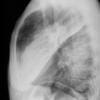

Case 2  Lingular pneum Lat

Date: 04/17/2005

Views: 7421